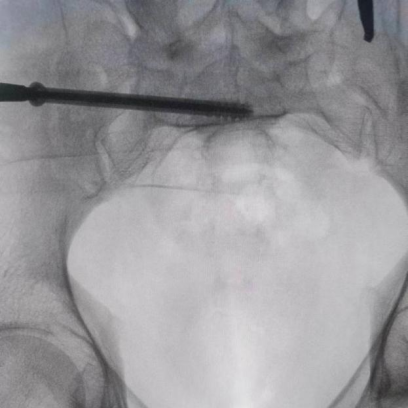

據(jù)了解,患者37歲,為高墜傷患者,入院合并顱腦挫傷、盆腔臟器出血、骨盆骨折多發(fā)傷患者。為最大限度降低手術(shù)風(fēng)險,同時給予患者滿意的手術(shù)療效,術(shù)前綜合評估患者病情,擬定行“天璣機器人”輔助定位下骨盆骨折微創(chuàng)手術(shù)。2月13日10時,手術(shù)正式開始。拉薩市人民醫(yī)院采集患者術(shù)中二維影像,通過骨科手術(shù)機器人擬定螺釘打入位置方向后,吳宏華主任完成手術(shù)設(shè)計,成功為該患者置入了一顆高難度骶髂螺釘,出血5ml,切口1cm。術(shù)后圖像顯示,螺釘位置及方向完全符合手術(shù)規(guī)劃,沒有一絲偏差,手術(shù)最終獲得圓滿成功。

圖為透視下見置入的骶髂螺釘,位置、長度精準(zhǔn),無絲毫偏差